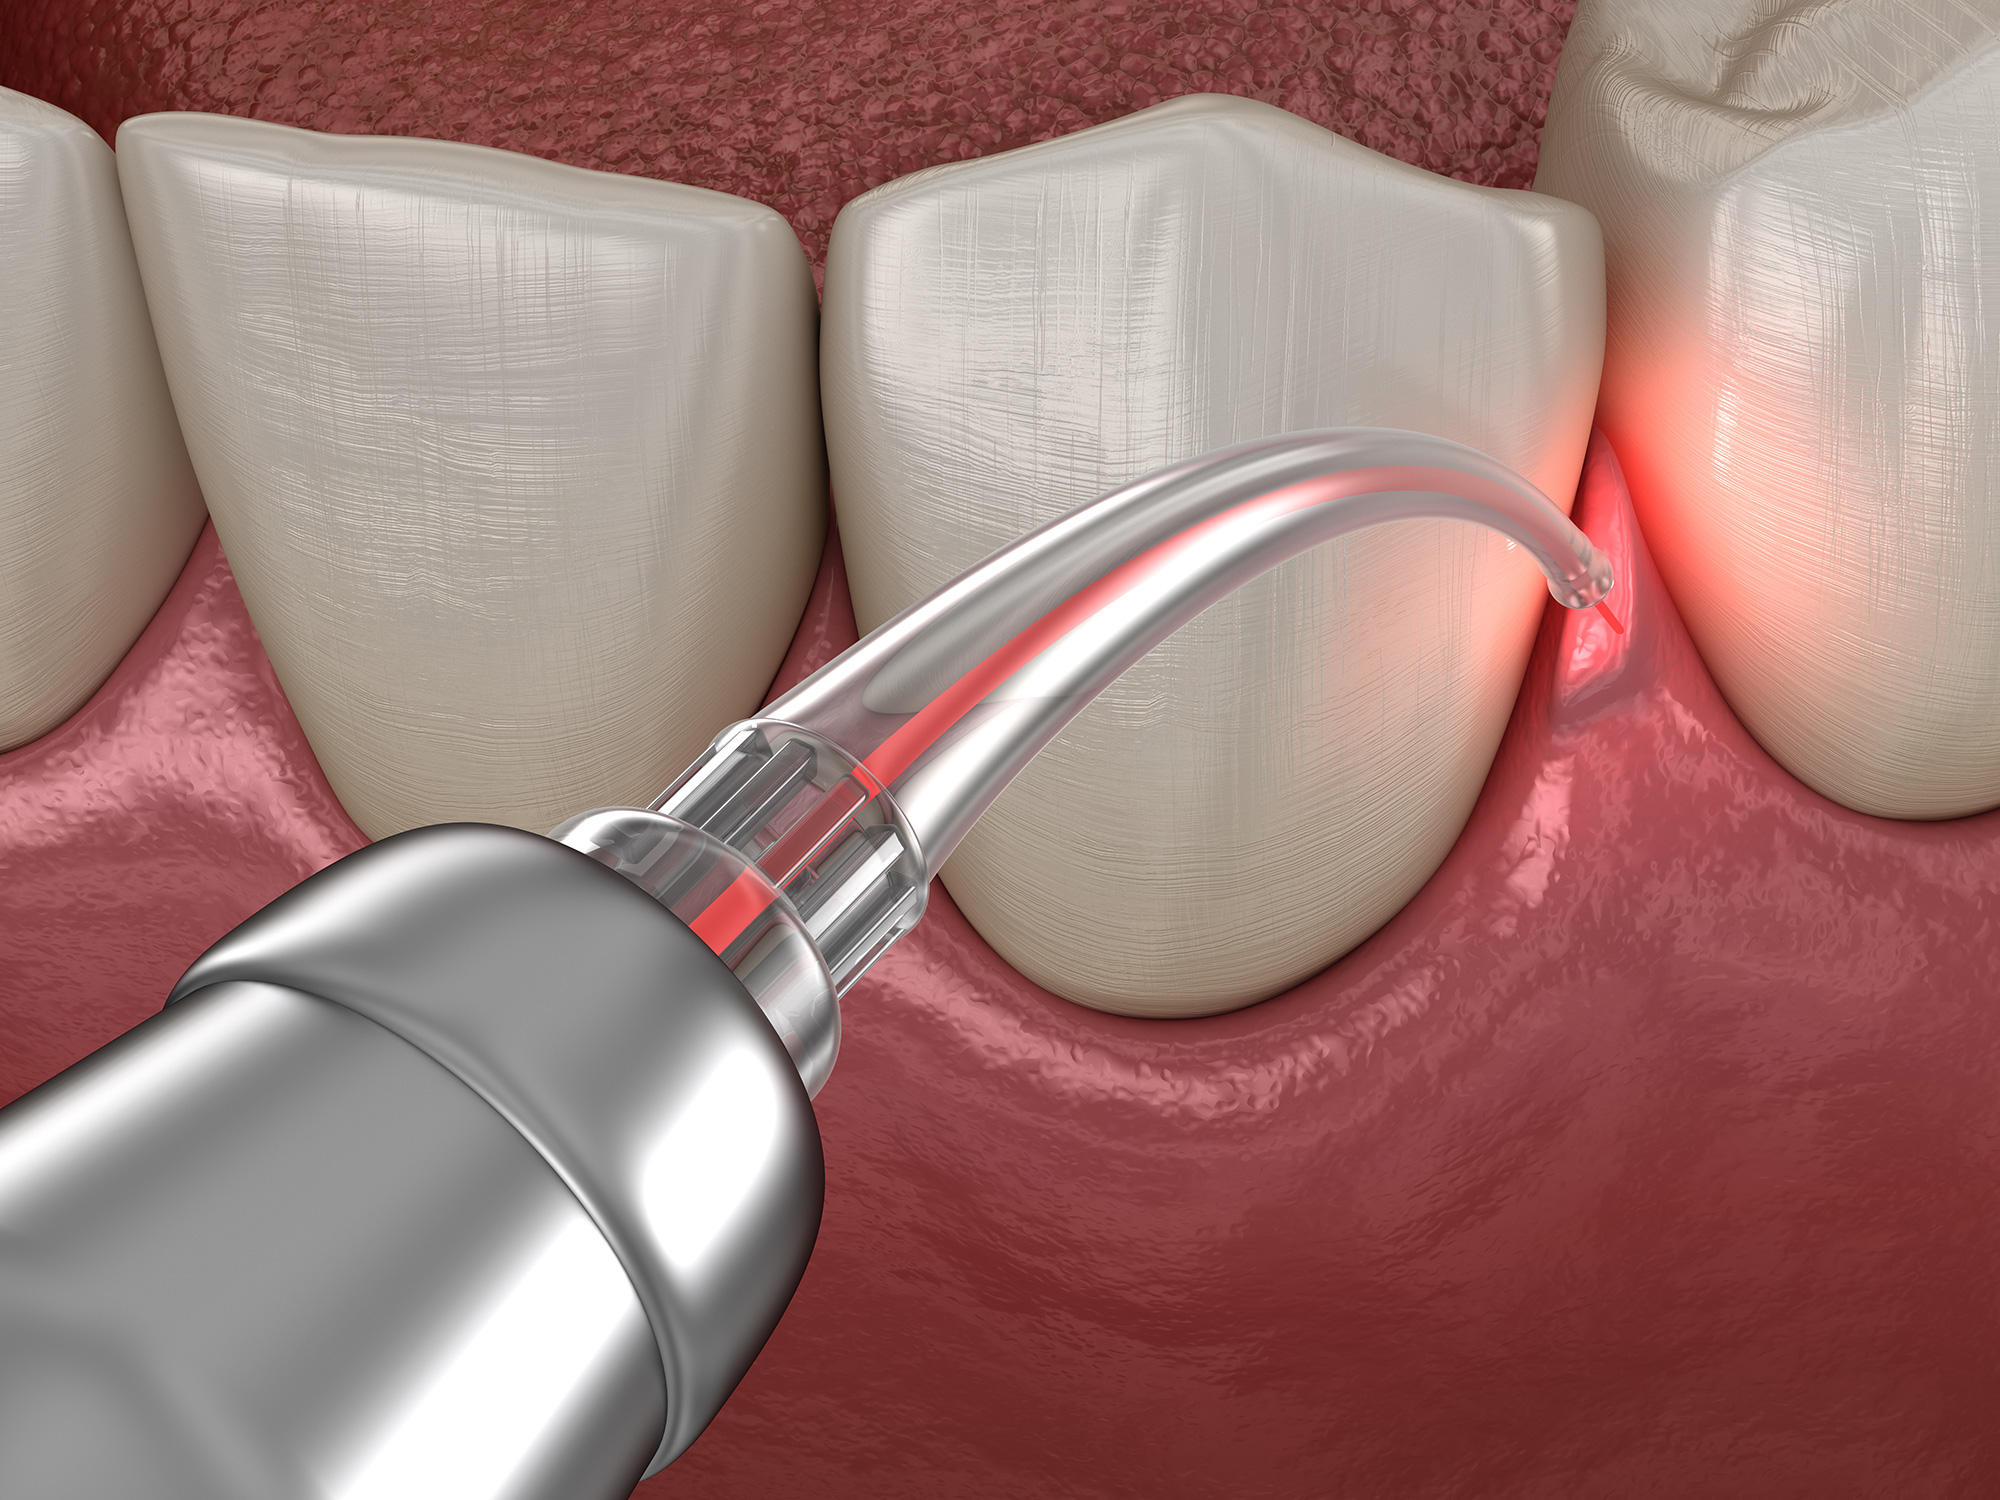

Фото и примеры имплантации зубов при пародонтите

Раздел: Необычные решения